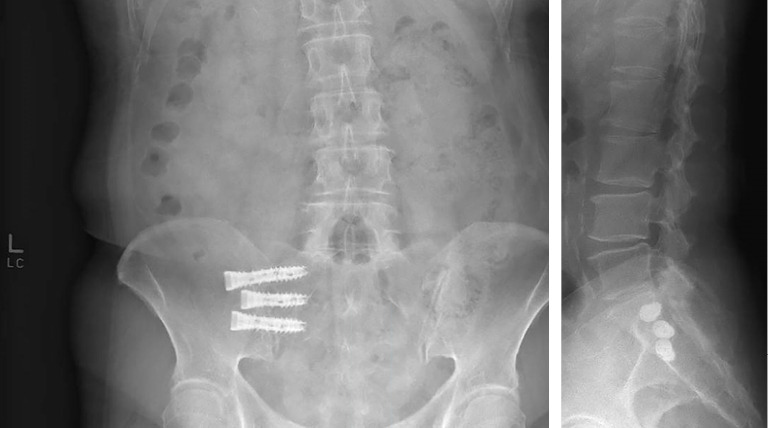

Case description: We present the case of a 76-year-old woman with a 1-year history of progressive left-sided low back pain that progressed along an S1 radicular distribution and became debilitating, interfering with their activities of daily living. Specifically, the pain radiated along the left buttocks, down the posterior aspect of the leg, and into the heel. SPECT/CT demonstrated non-specific, symmetric radiotracer uptake within the bilateral SI joints. She had a positive response to two SI joint injections. The patient was ultimately treated with a SI joint fusion. This case raises questions regarding the sensitivity and specificity of SPECT/CT for SI joint pain. A minimally invasive surgery (MIS) lateral SI joint fusion using navigated and fenestrated screws can provide significant pain relief.